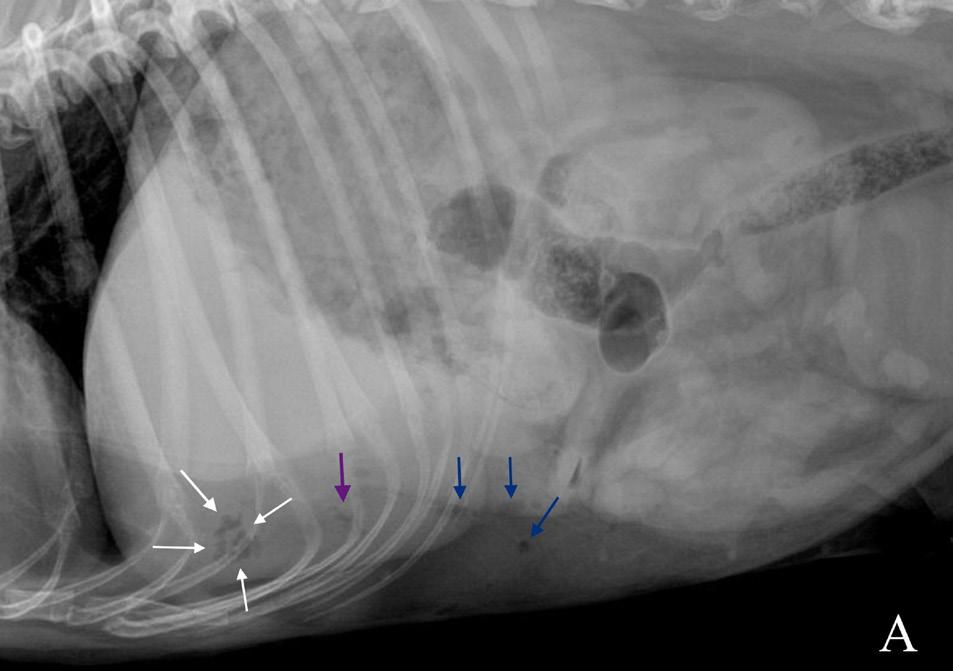

El examen neurológico evidenció paraparesia no ambulatoria y retraso en las reacciones posturales de ambas extremidades posteriores, más marcado en la extremidad posterior izquierda (EPI) (Fig.1). Los reflejos patelar, flexor y perineal estaban disminuidos y la nocicepción, intacta. El paciente presentaba parálisis de la cola con pérdida de nocicepción. La exploración de los pares craneales y las extremidades anteriores fue normal. No se detectó dolor espinal durante la evaluación. El examen neurológico fue compatible con una lesión localizada entre los segmentos espinales L4-S3.

Las pruebas diagnósticas realizadas incluyeron análisis de sangre, radiografía laterolateral de tórax y ecografía abdominal, sin resultar en alteraciones significativas. La serología frente al virus de la leucemia e inmunodeficiencia felina resultó positiva para esta última. En el estudio de resonancia magnética (RM; Fig. 2) de la región toracolumbosacra (Toshiba Vantage Elan 1.5 T: Adquisición de planos transversal, sagital y coronal ponderados en T1 pre y post-contraste intravenoso con gadolinio, así como planos ponderados en T2 y STIR) se cuentan 6 vértebras lumbares, lo cual es compatible con anatomía de transición en la región lumbar, como hallazgo incidental. En el lado izquierdo del canal vertebral, desde el tercio craneal de la vértebra L5 hasta el tercio caudal de la vértebra L6 se encuentra una lesión con aspecto alargado y de base ancha, con márgenes mal definidos e irregulares, distribución posiblemente extradural y/o intradural/extramedular, causando compresión severa de la médula espinal, que aparece desplazada hacia el lado derecho. En cuanto al patrón de intensidad de la señal, este fue hiperintenso de forma homogénea en las secuencias ponderadas en T2 e isointenso en las secuencias ponderadas en T1, con un realce homogéneo y focal en la región media de la vértebra L6. La lesión se extiende parcialmente en el foramen intervertebral izquierdo entre las vértebras L5 y L6 y se aprecia siringomielia leve, que puede ser un proceso secundario a la compresión de la médula espinal por parte de la lesión, más caudalmente a nivel lumbar.

El diagnóstico diferencial incluye procesos neoplásicos, como meningioma, linfoma o un tumor de la vaina mielínica como opciones más probables, siendo un origen inflamatorio de la lesión poco probable.

Figura 2. Imágenes de RM postcontraste en las que se identifica una lesión de forma alargada y ancha en su base, con distribución posiblemente extradural y/o intradural/extramedular a nivel de la vértebra L6 (flechas rojas). (A) Secuencia dorsal en STIR. (B) Secuencia transversal en T2. Nótese la compresión severa a la que es sometida la médula espinal (flecha verde). (C) Secuencia transversal en T1 precontraste. (D) Secuencia transversal en T1 postcontraste. M: masa; SC: médula espinal; R: derecha; L: izquierda.

Figura 1. Gato común europeo macho castrado de 7 años con pérdida del tono muscular de la cola y ausencia de propiocepción en ambas extremidades pélvicas.